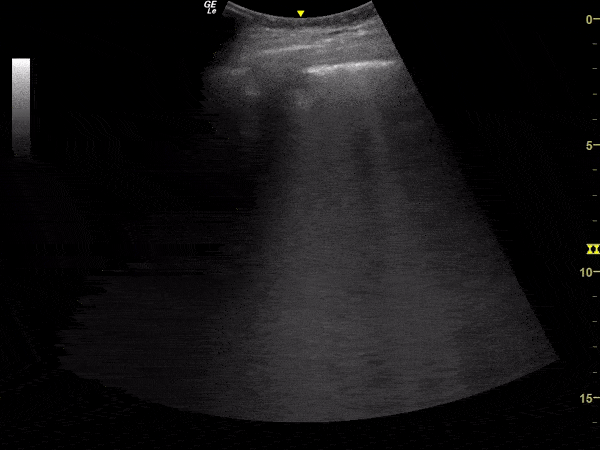

Pulmonary - Subpleural Consolidation in Suspected COVID-19 Pneumonia

This lung ultrasound clip demonstrates a subpleural consolidation in a patient with suspected pulmonary involvement by COVID-19. The clip is taken from an exam performed on an elderly male with flu-like symptoms for 14 days with progressive respiratory failure. Image courtesy of Renato Melo, Emergency Physician at Hospital das Clinicas de MarĂ­lia-SP, Brazil. PocusJedi (@JediPocus) associated.